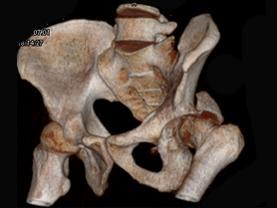

问题 男,44岁,有外伤史,请结合所提供的图像,选择最佳答案 ( )

选项 A、左髂骨骨折 B、左坐骨骨折 C、左髋关节脱位 D、左髋臼骨折并左髋关节脱位 E、左髋臼骨折

答案 D